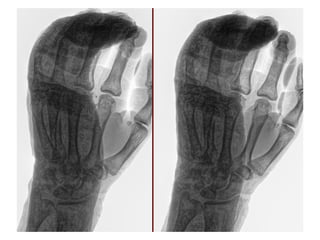

Diagnósticos: FRACTURA DIAFISIARIA DE 4TO MTC Y FRACTURA DE LA BASE DEL 5TO MTC MANO IZQUIERDA

Cirugía Proyectada: REDUCCION CERRADA Y FIJACION PERCUTANEA CON CLAVILLOS K A 4TO Y 5TO MTC MANO IZQUIERDA

Material OSS Solicitado: CLAVILLOS K

NOMBRE:LOPEZ GOMEZ CECILIA NSS:76236101671F1961OR URGENCIAS A Edad: 64 AÑOS Comorbilidades: NINGUNA Fecha de la lesión: 20/09/25 Mecanismo de lesión: CAIDA DE PROPIO PLANO DE SUSTENTACION Laboratorios: DENTRO DE NORMALIDAD Valoraciones: NA Diagnósticos: FRACTURA DIAFISIARIA DE 4TO MTC Y FRACTURA DE LA BASE DEL 5TO MTC MANO IZQUIERDA Cirugía Proyectada: REDUCCION CERRADA Y FIJACION PERCUTANEA CON CLAVILLOS K A 4TO Y 5TO MTC MANO IZQUIERDA Material OSS Solicitado: CLAVILLOS K